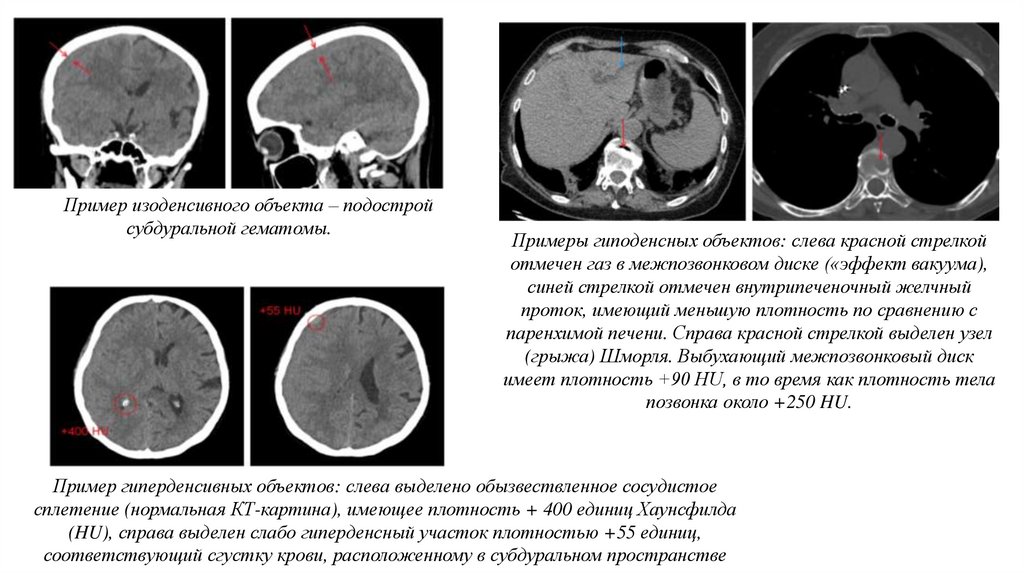

Пример изоденсивного объекта – подострой

субдуральной гематомы.

Примеры гиподенсных объектов: слева красной стрелкой

отмечен газ в межпозвонковом диске («эффект вакуума),

синей стрелкой отмечен внутрипеченочный желчный

проток, имеющий меньшую плотность по сравнению с

паренхимой печени. Справа красной стрелкой выделен узел

(грыжа) Шморля. Выбухающий межпозвонковый диск

имеет плотность +90 HU, в то время как плотность тела

позвонка около +250 HU.

Пример гиперденсивных объектов: слева выделено обызвествленное сосудистое

сплетение (нормальная КТ-картина), имеющее плотность + 400 единиц Хаунсфилда

(HU), справа выделен слабо гиперденсный участок плотностью +55 единиц,

соответствующий сгустку крови, расположенному в субдуральном пространстве